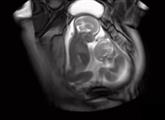

实拍双胞胎子宫里“抢地盘”:网友神回复

孩子的降生对一个家庭来说绝对是最好的礼物,而如果是双胞胎的话,那更是喜上加喜。 不过,别看父母乐得合不拢嘴,但双胞胎自己却是在还未降生之时便开始为自己的生存地位而“战”。...【